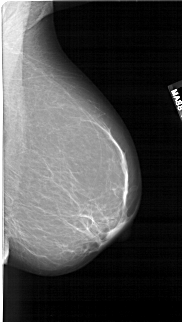

A_1860_1.RIGHT_CC

RIGHT_MLO LINES 6106 PIXELS_PER_LINE 3451 BITS_PER_PIXEL 12 RESOLUTION 43.5 NON_OVERLAY